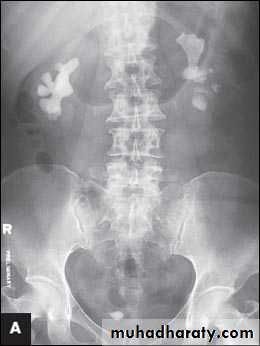

High density renal stonesStage horn calculus KUB filmsradio opaque stones